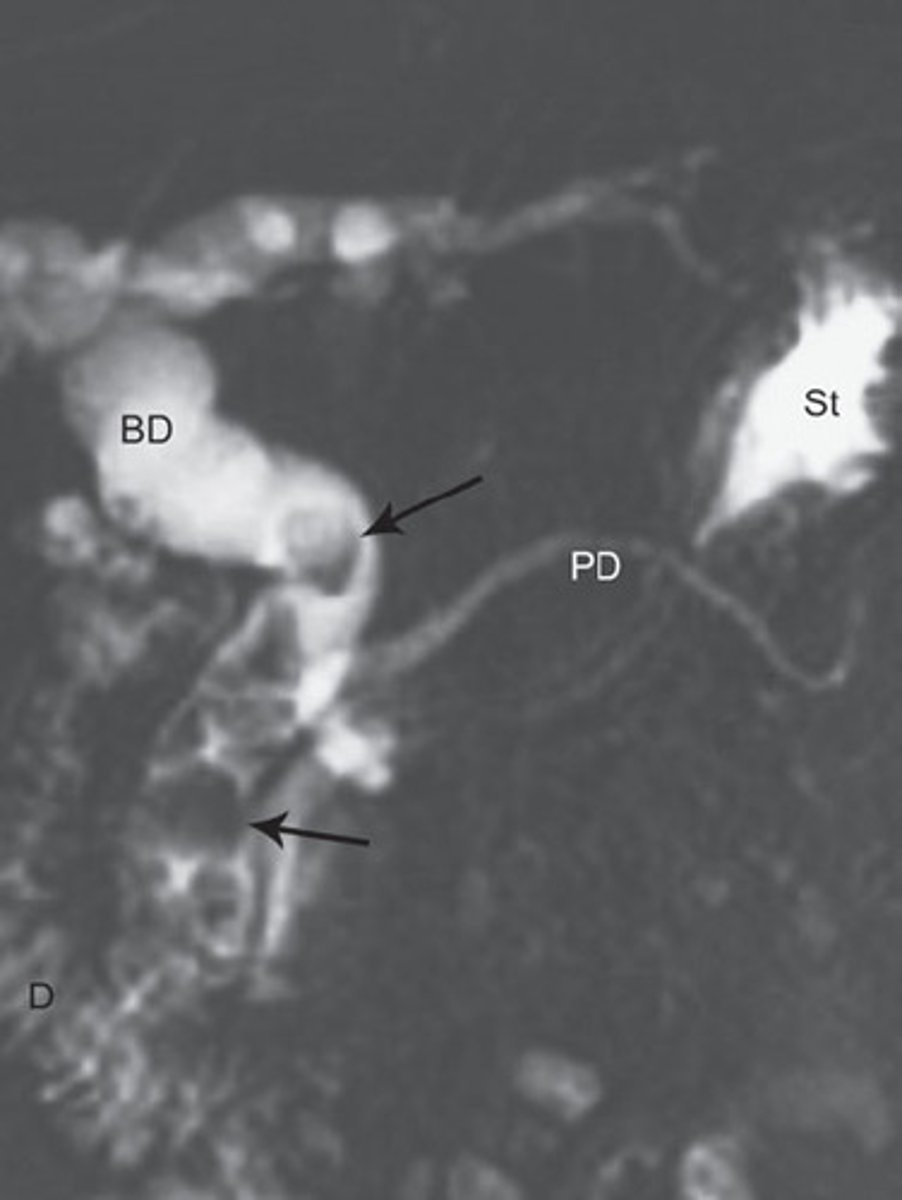

Primary Sclerosing Cholangitis (PSC)

Define Condition:

Autoimmune condition causing inflammation and obliterative fibrosis of intrahepatic and extrahepatic bile ducts

-Dx:

> Cholangiogram: confirms Dx

>> ERCP & MRCP

>> Shows alternating strictures and dilation "beading" of intra- and extrahepatic bile ducts